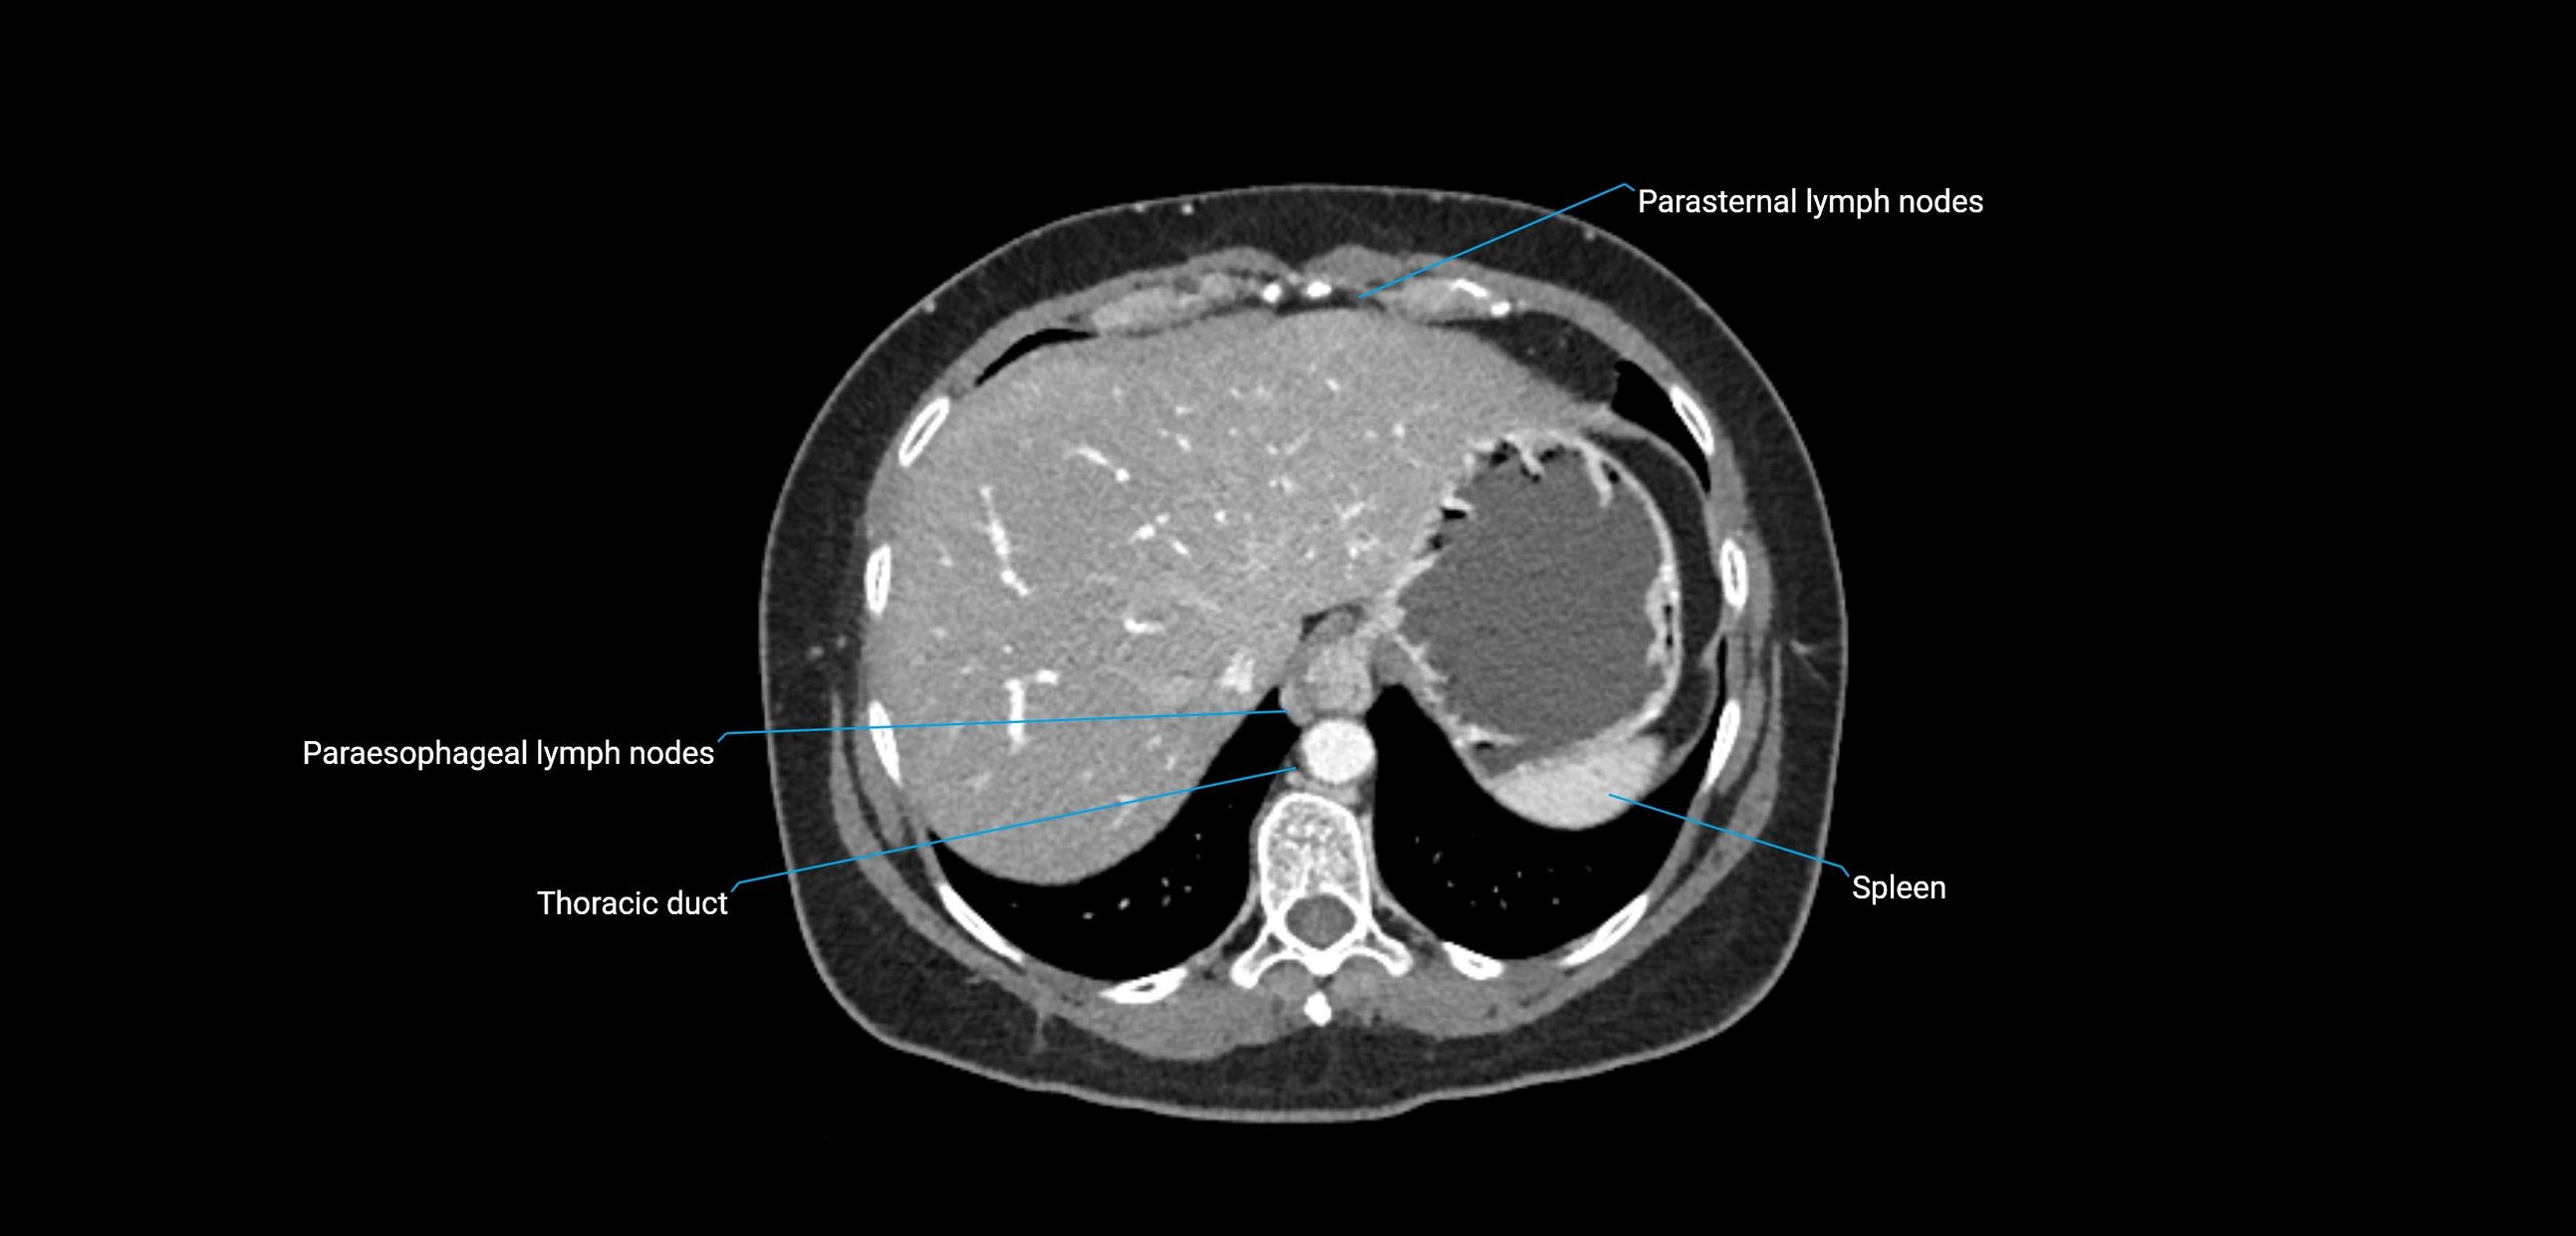

CT image

image